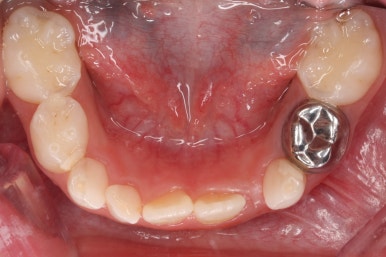

부산어린이치아교정 키다리아저씨치과에 처음 내원하셨을 당시의 입안의 모습입니다. 네 군데 모두 어금니는 보이지 않습니다.

입 안에서 문제점이 발견되지 않는 경우 일이 커지는 경우가 많은데 이번 환자분은 X-ray를 찍어봄으로써 문제를 조기에 발견하고 치료를 할 수 있었습니다.

X-ray 촬영이 신의 한수 였던 것이지요.